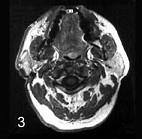

女性,55岁。右耳垂下无痛性肿块逐渐缓慢长大6年。触诊肿块界线清楚,活动,约4cm×5cm大小,表面呈结节状,中等硬度,与皮肤无黏连。

CT 检查结果如图,该病最可能的诊断是 ( )

女性,55岁。右耳垂下无痛性肿块逐渐缓慢长大6年。触诊肿块界线清楚,活动,约4cm×5cm大小,表面呈结节状,中等硬度,与皮肤无黏连。 CT 检查结果如图,该病最可能的诊断是 ( )

A皮脂腺囊肿

B腮腺腺淋巴瘤

C腮腺多形性腺瘤

D耳下淋巴结转移癌

E慢性淋巴结炎